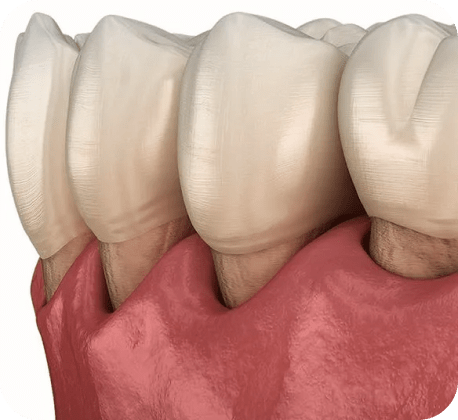

Неполноценный зубной ряд

Оставшиеся зубы смещаются.

- Возможность установки при средней и ярко выраженной убыли кости, а также при заболеваниях пародонта

- Более надёжная фиксация и распределение нагрузки

- Естественный внешний вид, удобство и комфорт